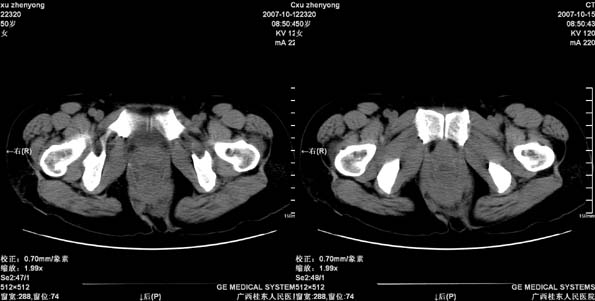

患者,女 50岁.会阴部坠胀感一月余,有痔疮病史,近期有便血;患者今年5月分结肠镜检查未见异常(由于患者不愿意ct增强扫描)没做增强,现准备手术,请各位老师会诊.

直肠壁明显增厚,呈块状表现,肠腔狭窄闭塞,考虑ca

直肠壁增厚明显,周围脂肪间隙模糊,见有小淋巴结显示,前方与阴道后壁分解不清。考虑直肠癌可能性大

不做强化,但平扫保留灌肠一定要做好。现在看直肠壁增厚明显,周围脂肪间隙模糊,前方与阴道后壁分界不清。考虑直肠癌可能性大

直肠左侧壁明显增厚,考虑直肠癌可能性大.